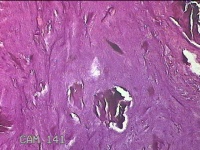

右侧中指指间关节背侧包块

性别

男

年龄

46岁

临床诊断

皮下结节

一般病史

发现右侧中指指间关节背侧一包块,伴间断性疼痛不适,考虑痛风结节。

标本名称

大体所见

灰白粉红色包块0.8x0.7x0.3cm一堆。